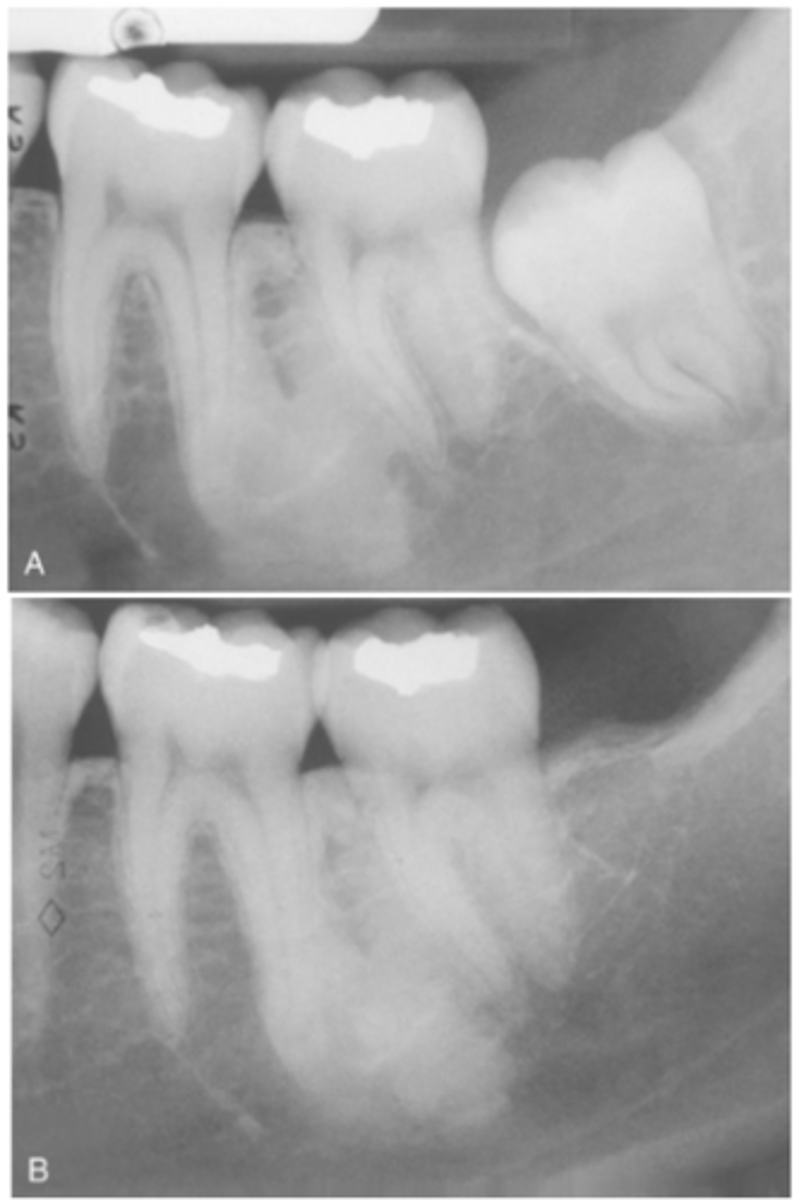

What do radiographic signs show in Idiopathic Osteosclerosis

Well-defined radiopacity

Most are associated to a root apex